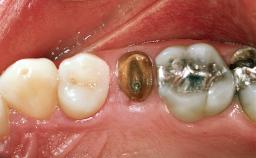

A healthy 26-year-old woman was referred for evaluation and treatment of her failing maxillary right central incisor (tooth 11). She reportedly traumatized the tooth at about age 9 and subsequently had repeated conventional and surgical endodontic procedures and fixed restorations. Despite these procedures, she had recurrent fistulas in the apical mucosa and a mid-facial pocket of 7 mm with suppuration. All other sites on the tooth probed 3 mm without inflammation. She presented with a medium biotype with triangularlyshaped teeth and a moderately high smile line, showing all of her papillas and a few millimeters of marginal gingiva in a full smile.Ceramic veneers were present on teeth 12, 21, and 22, and they were known to be somewhat bulky, eventually requiring replacement. She had a strong desire to avoid additional tooth preparation and would not consider a fixed dental prosthesis to replace tooth 11.